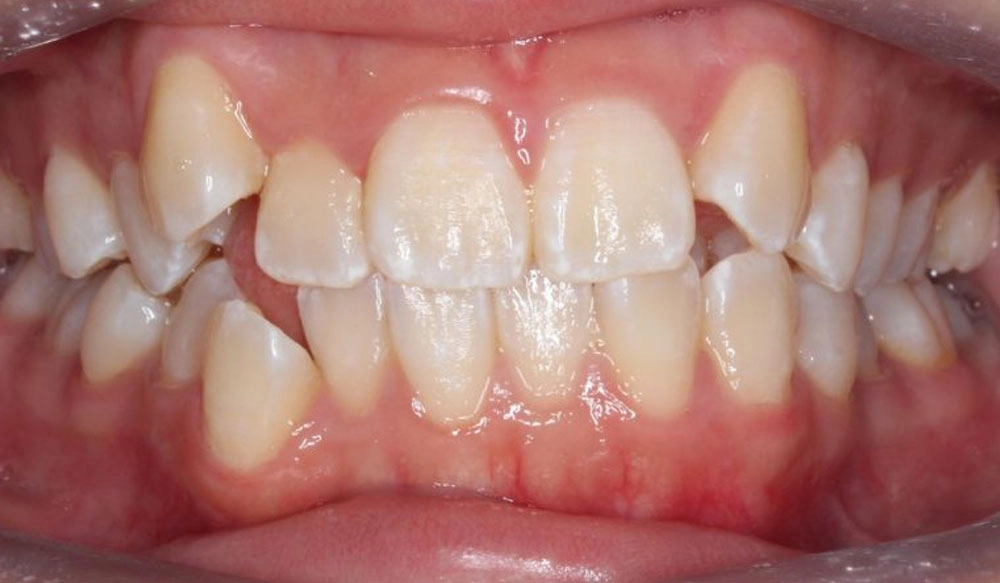

Crowding

Crowding is the condition in which there is a discrepancy between tooth size and space available for the teeth to be aligned in the dental arch

Patient Information:

Age: 17

Gender: female

Invisalign Treatment Option: Invisalign Comprehensive

Total Treatment Time:

29 months